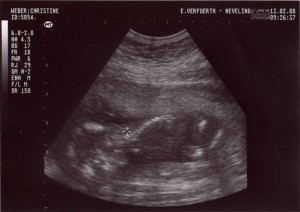

Ein paar Wochen später konnte man schon meinen Kopf …

… und auch den Rest meines Körpers erkennen.